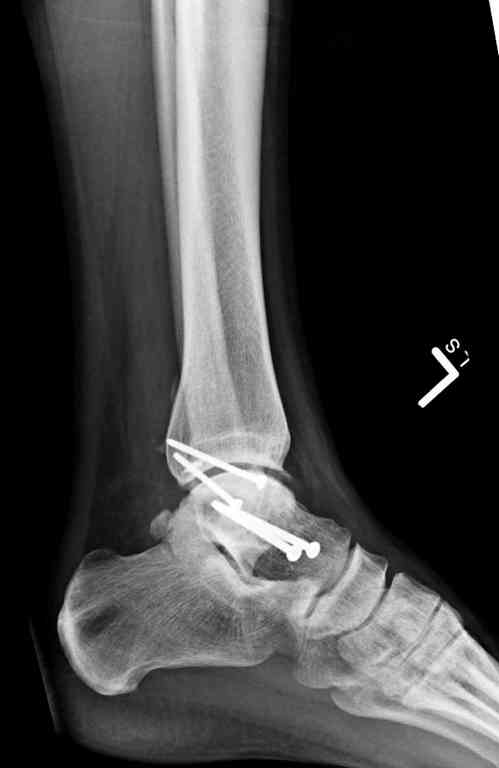

Переломовывих тарана с повреждением медиальной стороны. Через 4 часа после поступления проведена репозиция и фиксация тарана после Irrigation&Debridment. Частичное несращение медиальной лодыжки не беспокоит, вернулся к активному образу жизни. Полная нагрузка разрешена через 11 недель. Финальные снимки через 11 месяцев.

Прооперировали таранную кость, доступ внутренний без пересечения внутренней лодыжки. Хотя покаялись, что не пошли на остеотомию лодыжки внутренней. Винт

провели через небольшой передний доступ.